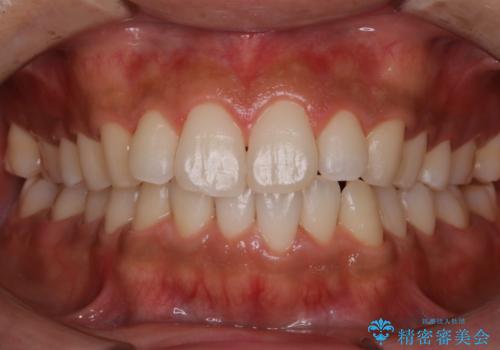

- 特に症状など気になるところはないが、メンテナンスして欲しいとのことでした。染め出しをしてのブラッシング指導とPMTC30分コースを行いました。

磨き残しが多くなると、お口の健康を維持していくのが難しくなってしまいます。お口の健康を守っていくためには、毎日のハミガキを行っていくのが基本です。そのため、なにか症状がなくても定期的に歯科医院で口の健康状態のチェックをすることが大切です。